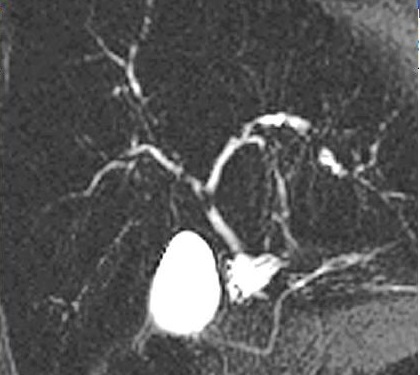

Image radiologique

cholangie-IRM recontruit en 3D de voie

biliaire extra et vintrahepatique . Image de calcul

primitive hypointense de voie biliaire gauche

( fleche rouge ) . Voie biliaire en amont est tres

dilate . Image cholangio-IRM en recontruit en 3D de

voie biliaire . |

Image des lithiases secondaire du

VGP et du canal hepatique gauche d'une cholangite

sclerosant primitive des voie biliaire . Dilataion

legere de voie biliaire en amont est en voyait ..

Image cholangio - IRM coupe 2D frontal |